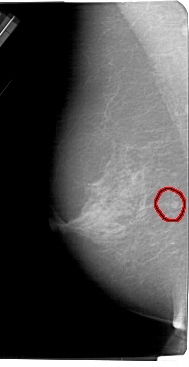

A_1337_1.LEFT_MLO

FILE: A_1337_1.LEFT_MLO.OVERLAY

TOTAL_ABNORMALITIES 1

ABNORMALITY 1

LESION_TYPE MASS SHAPE ROUND MARGINS ILL_DEFINED

ASSESSMENT 4

SUBTLETY 3

PATHOLOGY BENIGN

TOTAL_OUTLINES 1

BOUNDARY